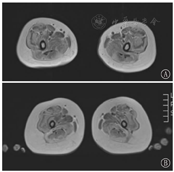

2例患儿下肢肌肉MRI T1加权像(T1WI)均示:大腿肌肉弥散脂肪化,单块肌肉受累边缘重中央轻,以股外侧肌明显,呈"三明治"征,股直肌中央亦有受累,缝匠肌、长收肌、股薄肌相对受累较轻。小腿水平弥散受累,以腓肠肌和比目鱼肌外侧受累为著(图3)。

本研究2例患儿肌肉MRI病变模式与UCMD患者下肢MRI研究一致[5] 。因MRI结果需高水平专家解释,故在神经肌肉疾病诊断中不作为常规基础检查,对特定患者,可作为鉴别诊断附加工具。

UCMD主要与Bethlem肌病相鉴别,二者为等位基因病。Bethlem肌病病情相对轻,进展缓慢,成人期仍有移动能力,呼吸肌受累不显著,寿命较少受影响[6],下肢肌肉MRI可见受累肌肉周边信号增高而中央相对正常,股外侧肌和股中间肌有同心脂肪浸润,股直肌可见"中心影"征或"U"形浸润[6]。本研究2例患儿起病早,呼吸肌受累早,肌肉MRI均可见股外侧肌呈"三明治"征,故目前临床支持考虑UCMD。